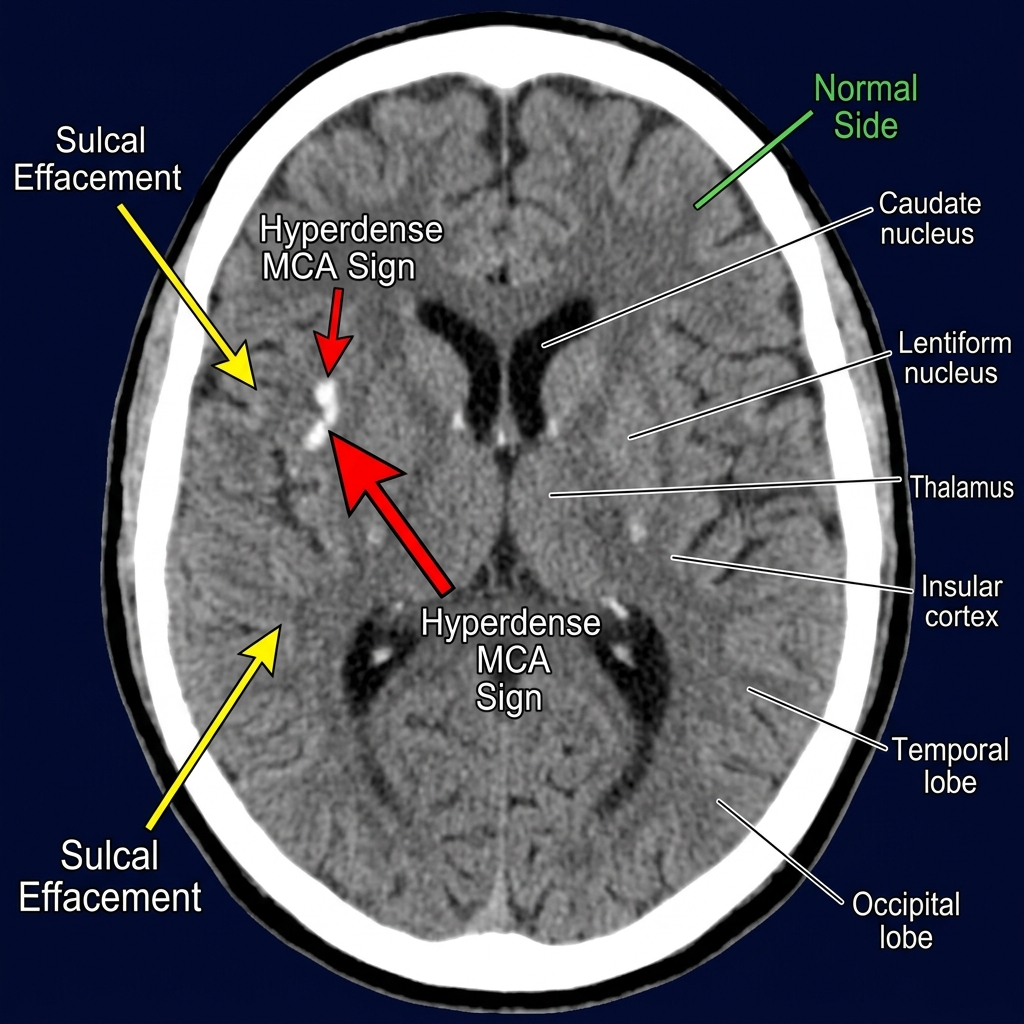

A comprehensive guide to interpreting CT brain imaging in acute stroke. Covers early ischemic signs, the ASPECTS scoring system, hemorrhage identification, CT angiography, and CT perfusion maps.